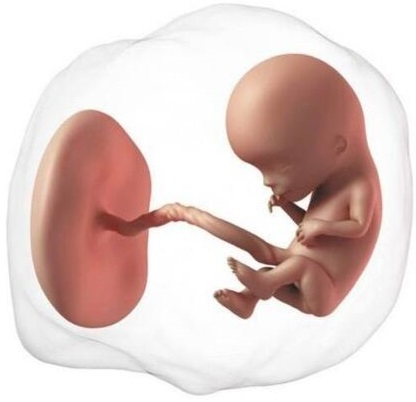

El embrión se alimenta de la vesícula vitelina, un pequeño anillo que se observa al lado del embrión cargado de nutrientes, pero ahora necesita mucho más oxígeno y alimento, tiene que usar la placenta.

En estas semanas ya se ha formado el cordón umbilical cuya función es llevar sangre hasta la placenta y devolverla al bebé; ahora empezará a depender de la placenta. Ésta última le proporciona oxígeno, nutrientes y agua, y elimina los desechos del metabolismo. Es importante recordar que las sustancias nocivas para el embrión como el tabaco, las drogas, los químicos o el alcohol también atraviesan la placenta.